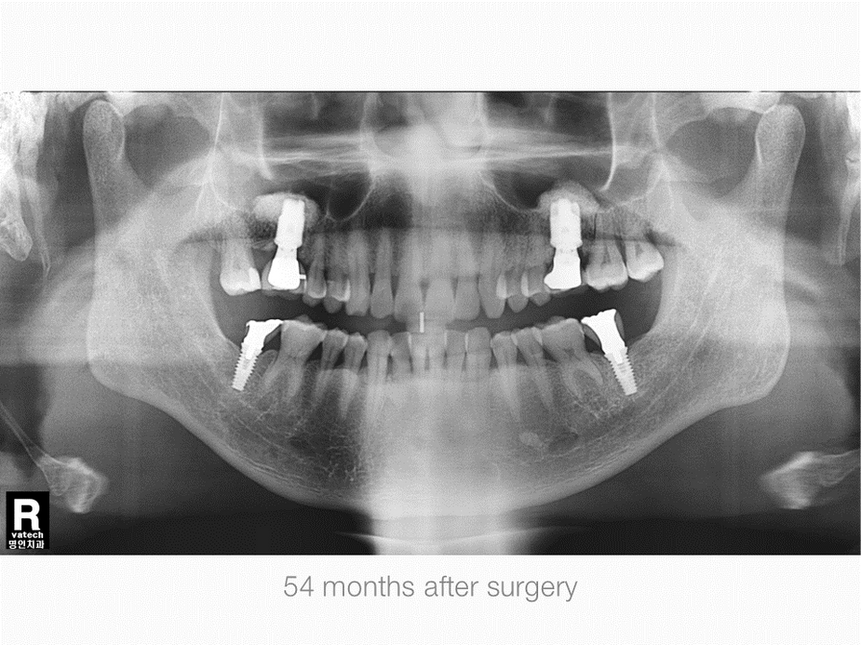

Right Maxillary, First Molar Area, Sinus & Crestal Augmentation

Gender: Male

Age: 53 years old

Operation Site: #16 Sinus Graft, Crestal Defect